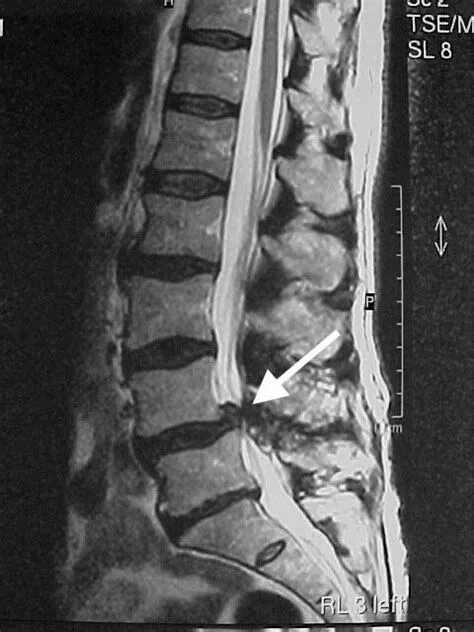

Спондилоартроз l4 s1 сегментов